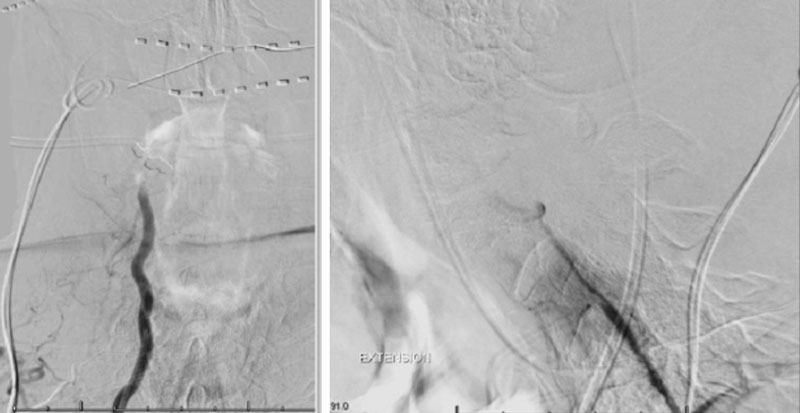

Dynamic provocative fluoroscopy failed to reveal significant Vertebral osseous instability (Figure 2A), however, Transcranial Doppler Flow velocities in the distal right Vertebral and Basilar Artery are markedly reduced during Extension of the Neck (Figure 2B).

During neutral positioning, the vertebrobasilar circulation fills briskly from the Right Vertebral Artery. (Figure 4)

On rotation to the left, the patient experienced mild symptoms, however no significant Vertebral Artery or basilar reduction in flow was observed. On rotation to the right, the patient experiences slightly more moderate symptoms, however no significant Vertebral Artery or vascular reduction flow was observed. On hyper extension of approximately 10-15 degrees, passively performed by the patient until symptoms are reproduced, angiogram demonstrates complete occlusion of the right Vertebral Artery at approximately the C2-C1 level. (Figure 5)